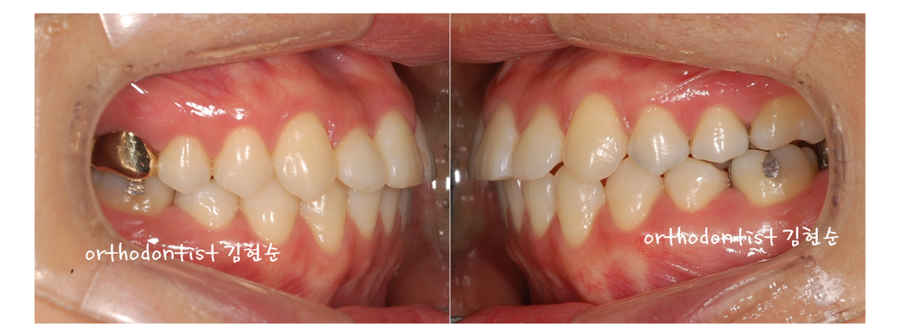

Ⅲ. 개방교합 비발치 세라믹 교정 후 개선 사항들

치아배열 소요기간 6개월,

미니스크류와 스프링을 이용해서

안으로 당긴 소요기간 6개월,

총 12개월의 기간으로

아래 사진들처럼

안면비대칭 개선을 위한

비발치 세라믹 교정이

잘마무리 되었습니다.

그럼 안면비대칭 교정

(비발치 세라믹 교정)의

전후 사진을 통해,

안면비대칭 교정 전후를

차분히 살펴보겠습니다.

위 아래의

좌측 사진들이

안면비대칭 치아교정 전,

우측 사진들이

안면비대칭 치아교정 후

입니다.

- 삐뚤빼뚤했던 치열이

가지런히 바르게

정열 되었습니다.

- 정면 사진에서 보이던

왼쪽의 치아틈이

사라졌습니다.

- 좌측으로 비대칭이던

안면비대칭이 완벽히

개선되었습니다.

4. 반대교합이던

부정교합이 정상교합으로

돌아오면서

위아래 치아들이

잘맞물리게 되었습니다.

그 결과로

- 음식물 섭취시 불편했던

저작기능이 개선되었습니다.

반대교합이던

부정교합의 불편한 발음 문제

또한 정상교합으로 돌아오면서

- 정확한 발음이 가능해졌습니다.